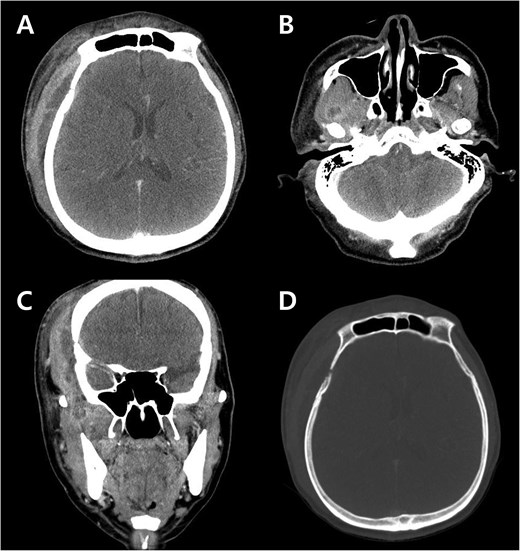

Contrast-enhanced CT revealed cellulitis at lateral pterygoid muscle and masseter muscle, and a 9.5 × 1.4 × 7.6 cm lobulated fluid collection in the right frontoparietal scalp, right masticator space and temporalis muscle, and adjacent soft tissue swelling and peripheral enhancement. There was focal bone erosion and a bone defect at the right lateral frontal bone, with adjacent dural thickening at the right frontotemporal convexity, suggesting intracranial extension of the inflammation (Fig. 2).

Preoperative contrast-enhanced CT images at emergency department. (A) Axial image shows a lobulated fluid collection beneath the scalp and temporalis muscle, with adjacent dural thickening below the suspected bony defect. (B) Axial image demonstrates cellulitis and abscess formation in the lateral pterygoid muscle. (C) Coronal image depicts the lateral pterygoid abscess extending through the lateral masticator space to involve the temporalis muscle. (D) Axial image shows bony erosion and bony defect of the right lower frontal bone.